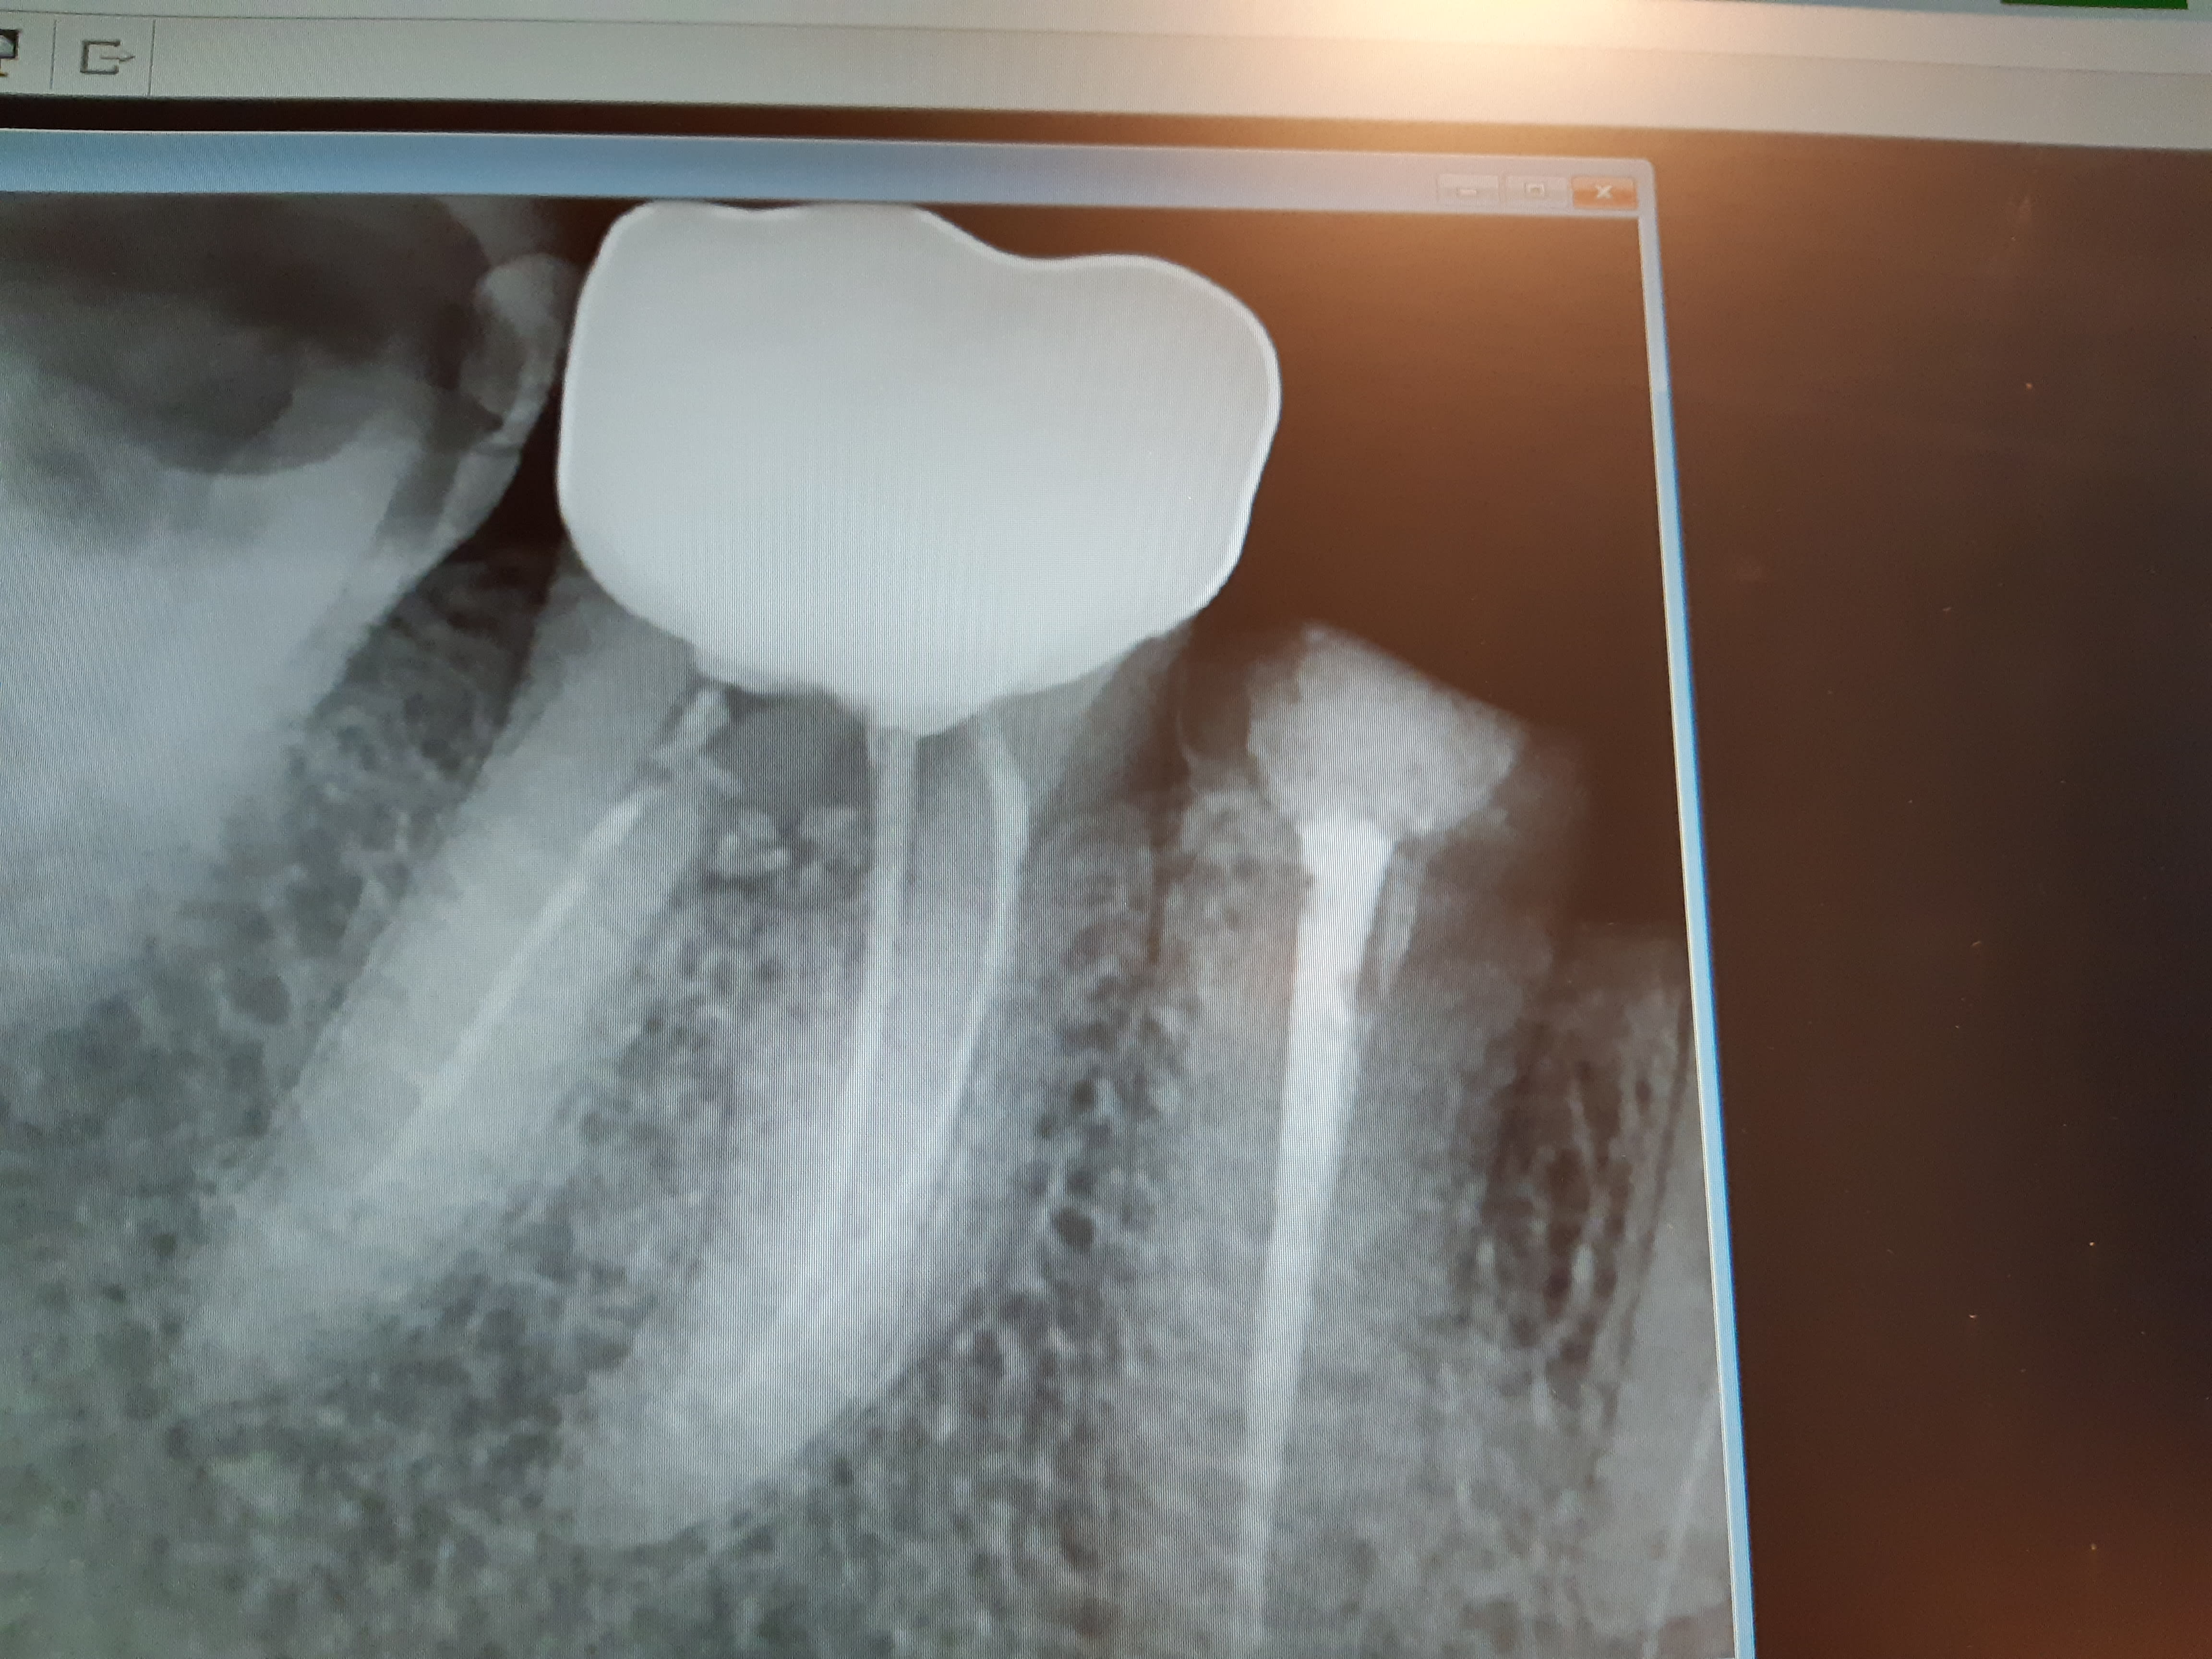

Un exemple joint de couronne sur dent très délabrée, c'était avant la préparation pour ic couronne. Pour vous vous avulsez la 45? (Oui y a un soucis sur la 46 aussi mais c'est autre chose ca et ce n'est pas moi qui ai faite la couronne sur celle ci).

20191220 180816 msny10 - Eugenol